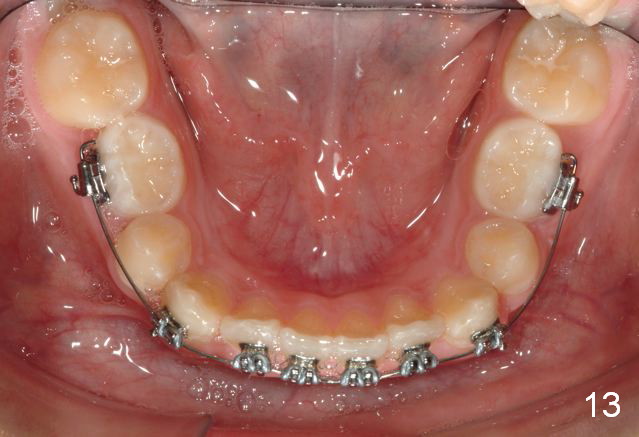

Brackets were placed on 2015_09_06 (Fig.11-13, Phase I pre-orthopedic tooth movement, leveling in advance of Herbst appliance therapy using ankylosed Es).   Six months later (Fig.14-16), LR7 did better, LL7 did not and will need intervention. But intrusion of L 3-3 looks good.